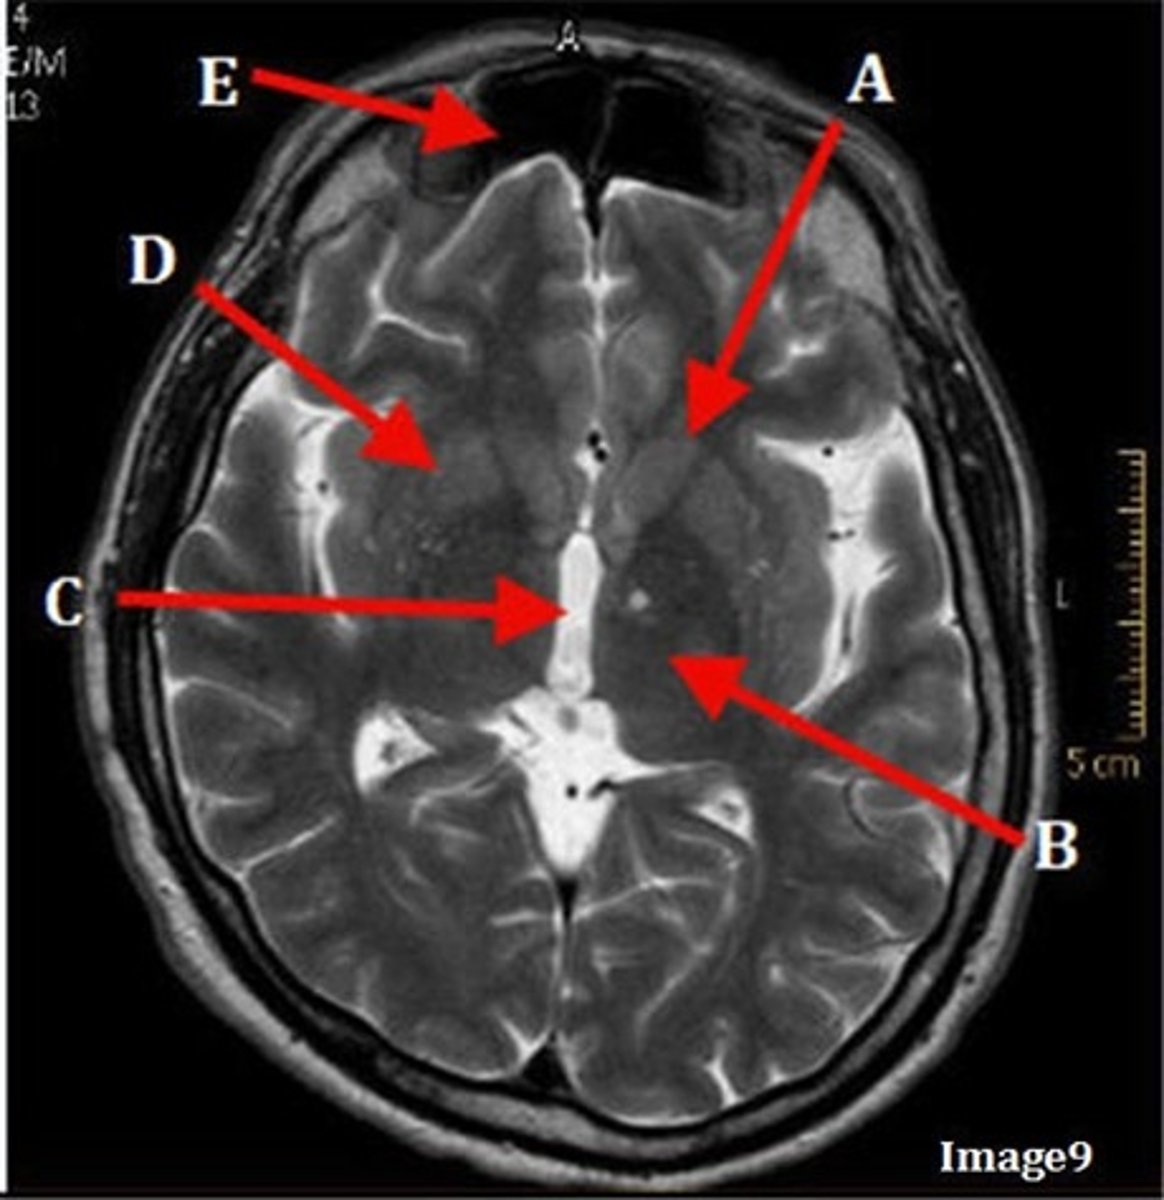

A

pituitary gland

B

lateral ventricle

C

corpus

E

fornix

F

internal carotid artery